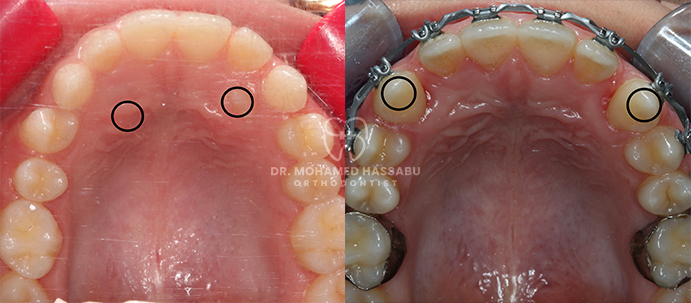

التقويم المعدني عبارة عن أدوات أسنان خاصة مصنوعة من الفولاذ المقاوم للصدأ تساعد في إصلاح الأسنان التي لا يتم محاذاتها بشكل صحيح. تحتوي هذه التقويمات على أقواس معدنية تلتصق بالأسنان وأسلاك رفيعة تعمل على تحريك الأسنان بلطف إلى الأماكن الصحيحة مع مرور الوقت. من خلال ارتداء هذا التقويم، تصبح الأسنان المزدحمة أو الملتوية مستقيمة تدريجيًا، مما يخلق ابتسامة جميلة لك ولطفلك.

تعتبر التقويمات المعدنية ضرورية للعناية بأسنان الأسرة بشكل عام لعدة أسباب. أولاً، إنها تعمل بشكل جيد في إصلاح مشاكل محاذاة الأسنان المختلفة مثل الأسنان المزدحمة أو المتباعدة أو العضة الزائدة أو السفلية. من خلال إصلاح هذه المشكلات في وقت مبكر، يمكن للتقويمات المعدنية أن تمنع حدوث مشاكل الأسنان الأكثر خطورة لاحقًا، مثل صعوبة المضغ أو التحدث. ثانياً، يساعد التقويم المعدني في الحفاظ على الأسنان أكثر نظافة وصحة لأنه يصبح من الأسهل تنظيفها والعناية بها عندما تكون محاذية بشكل صحيح. وهذا يقلل من فرصة الإصابة بالتسوس أو مشاكل اللثة، مما يجعل فمك أو فم طفلك أكثر صحة.

لقد كانت التقويمات المعدنية حلاً موثوقًا ومثبتًا لتقويم الأسنان لأجيال عديدة. إنها فعالة للغاية في تصحيح مشاكل الأسنان المختلفة، بما في ذلك الأسنان المزدحمة، والفجوات، والعضة العلوية، والعضة السفلية. من خلال الضغط بلطف على الأسنان مع مرور الوقت، تقوم التقويمات المعدنية بنقلها تدريجياً إلى مواقعها الصحيحة، مما يخلق ابتسامة متناغمة ومتماسكة.

يقوم التقويم المعدني بتصحيح مشاكل محاذاة الأسنان بشكل فعال، مما يؤدي إلى ابتسامة أكثر صحة وجاذبية.